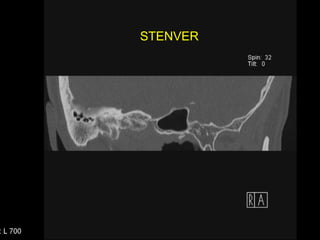

Proyección de StenverPerpendicular al plano de PöschlTambién es en 45° oblicuo al plano coronal y sagital, pero rotado en 90° Muestra las vueltas de la cóclea y  en  sección de corte la cortical superior del CSS

STENVERSTENVER

Stenver Derecho

Stenver Izquierdo